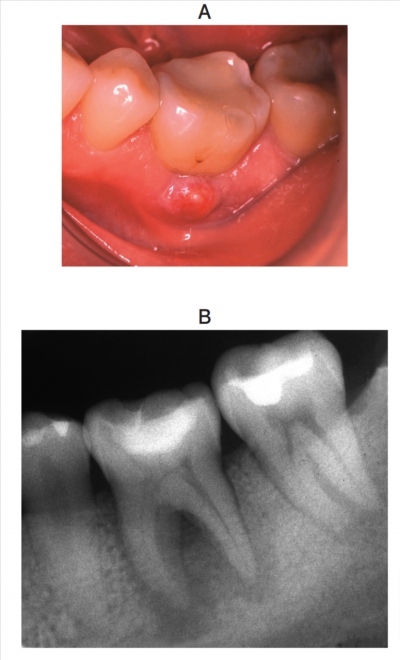

37歳の女性。左側の下顎第一大臼歯部の歯肉腫脹を主訴として来院した。2か月前に気付いたが、痛みがないためそのままにしていたところ徐々に大きくなったという。⎾6 は軽度の打診痛があり歯髄電気診に反応しない。初診時の口腔内写真とエックス線写真を別に示す。歯周組織検査結果の一部を表に示す。

適切な処置はどれか。1つ選べ。